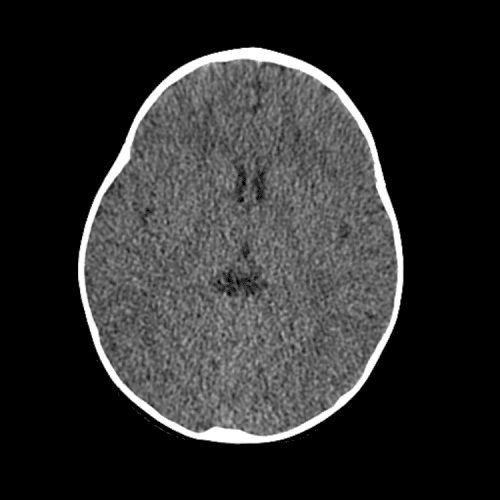

Non-traumatic Head CT Cases

Classic Cases

Includes classic examples of cases commonly seen on call.